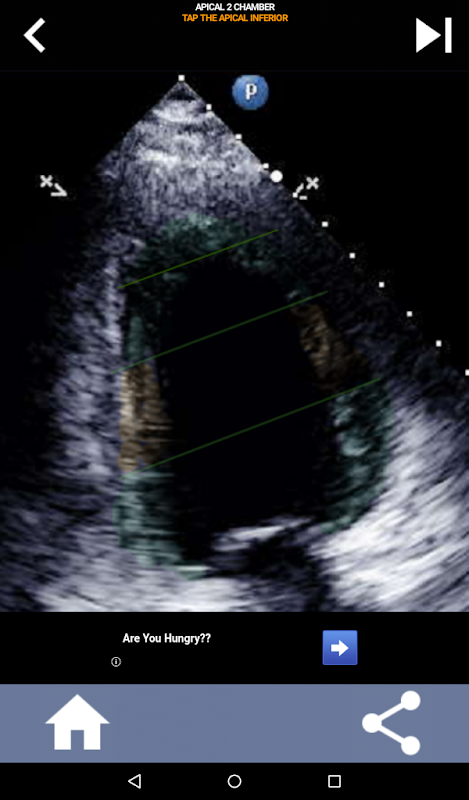

Enfoque visual basado en cuestionarios para aprender los segmentos cardíacos de la AHA: ecocardiografía

Comprender los segmentos cardíacos de la AHA (Asociación Estadounidense del Corazón) es de suma importancia para que un ecografista cardíaco se comunique de manera efectiva con el cardiólogo que escribe el informe. Al conocer las regiones anatómicas específicas y sus segmentos correspondientes, el ecografista puede describir y comunicar con precisión cualquier anomalía o hallazgo, asegurando una comunicación clara y concisa entre ambos profesionales.

Esta comprensión se vuelve particularmente crucial cuando el cardiólogo busca determinar la ubicación precisa de un problema o cuando el médico de guardia identifica un problema dentro de una región específica, lo que hace que el ecografista muestre con precisión el segmento correspondiente, como la pared inferior media. Por lo tanto, poseer una comprensión integral de los segmentos cardíacos de la AHA es un conjunto de habilidades esencial.

Esta aplicación pondrá a prueba su conocimiento utilizando imágenes de eco reales, que a menudo encuentro que es el mejor método de enseñanza.